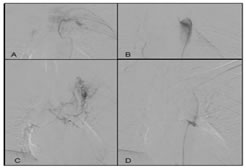

Figure 3:

CASE3: Left upper lobe mass in 23 years female, causing recurrent hemoptysis.

Angiogram showed mass supplied by a left 2nd intercostal artery and Hypertrophied bilateral bronchial arteries with common origin. The culprit vesels were embolised selectively by 500 micron PVA particles. Patients hemoptysis stopped completely.